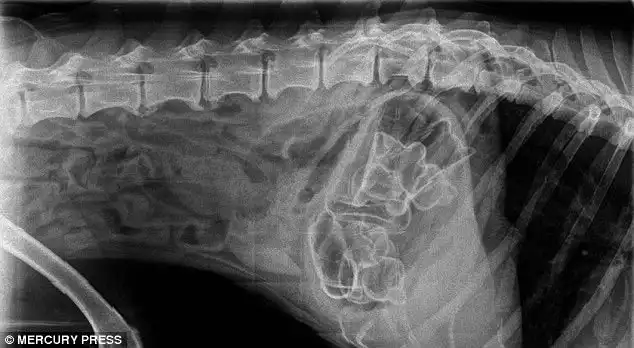

Доберман Зевс, съевший 26 мячей для гольфа

Все 26 мячей извлеченные из его живота